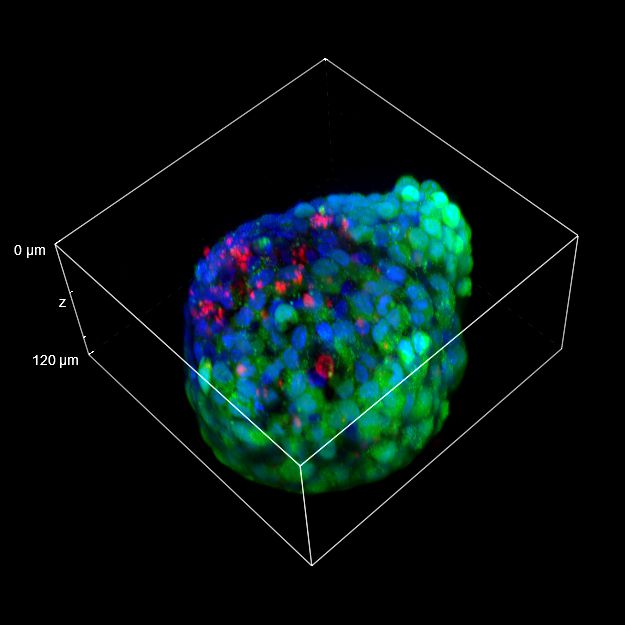

To better appreciate the 3D cellular organization, in Figure C we show a volume view (120 um thickness) of the same spheroid acquired with both objectives, showing the staining even in the deeper regions of the 3D cancer spheroid. Finally, in Figure D, a 3D movie of the whole spheroid acquired with the 25x silicone oil objective is shown.

The comparison between the images acquired with the 20x air objective and those with the 25x silicone oil objective (Figure A, B and C) highlights the importance of the lens choice based on the biological application. The transition from 20x to 25x leads to a gain in resolution (based on the greater NA of the 25x compared to the 20x NA), which certainly affects the image quality, and also leads to a reduction in the light refraction. As a matter of fact, immersion oils greatly improve the microscope’s resolving power by replacing the air gap between the lens and the coverslip with a higher refractive index medium, thus allowing to reduce the refraction of light.

In 3D imaging, matching the refractive index of the sample and its immersion medium is crucial for deep tissue observation. Silicone immersion oil is perfect for imaging through thick biological samples; it closely matches the refractive index of cells and of the mounting medium, decreasing spherical aberration and resulting in brighter and higher resolution images compared to those acquired with a common 20x air objective.

Figure C 3D tumor spheroids: 3D volume view of a spheroid acquired with 20x air objective (LEFT) and 25x silicone oil objective (RIGHT). Living cells are marked with Calcein (green) and dead cells with PI (red). Nuclei are stained with Hoechst (blue). Scale bar along Z-axis: 120 um. These images were acquired with CrestOptics X-Light V3 spinning disk.